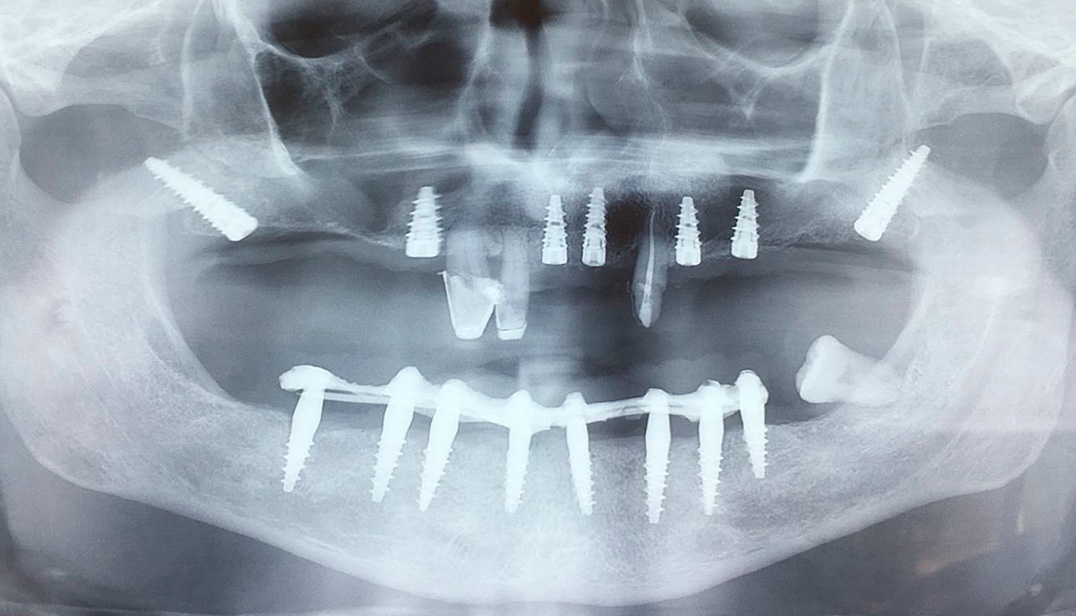

The pterygoid implants

The pterygoid implant is a dental implant that is installed behind in the upper dental arch, has an average length of 18 mm, which, starting from the maxillary tubercle, intersects the bony plates of the pterygoid fossa. The operation is performed under local anesthesia and lasts an average of about 20 minutes.

In addition, if conditions meet the requirements, a fixed temporary prosthesis can be placed within 24 hours after placement of the implants (immediate loading) emerging from the alveolar bone. At the end of the osseointegration period, the temporary prosthesis is replaced with a final fixed ceramic prosthesis. In cases of complete edentulism, the rehabilitation of the entire superior arch is obviously carried out by combining tuberous-pterygoid implants with other types of implants distributed in other areas of the mouth to provide a fixed prosthesis with a large number of attachment points.